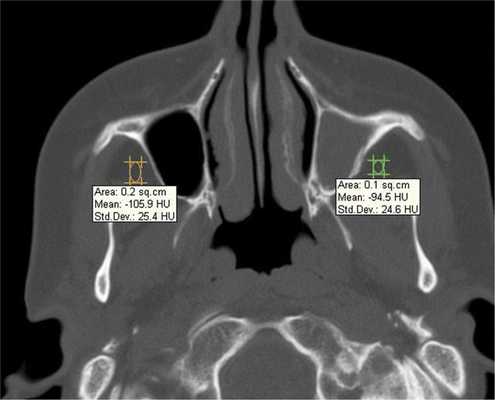

Воспалительные изменения слизистой оболочки верхнечелюстной пазухи, существующие в течение длительного времени, вовлекают в процесс костную стенку. На компьютерных томограммах отмечается утолщение костной стенки в костном режиме и появление «оптического эффекта» — уплотнение стенки в 1,5—3 раза за счет отека надкостницы — при просмотре в мягкотканом режиме (рис. 1, а, б) [9]. При одностороннем процессе, характерном для одонтогенного поражения, на контралатеральной интактной стороне такого эффекта не определяется.

Рис. 1. Рентгеновская компьютерная томограмма околоносовых пазух. Коронарная проекция: мягкотканное окно (а) и костное окно (б).

При воспалительных изменениях в ретроантральной жировой клетчатке верхнечелюстной пазухи на РКТ повышаются денситометрические значения ее плотности [10]. При одностороннем процессе отмечается выраженная асимметричность значений плотностей (рис. 4).

Рис. 4. Рентгеновская компьютерная томограмма околоносовых пазух. Аксиальная проекция, костное окно.